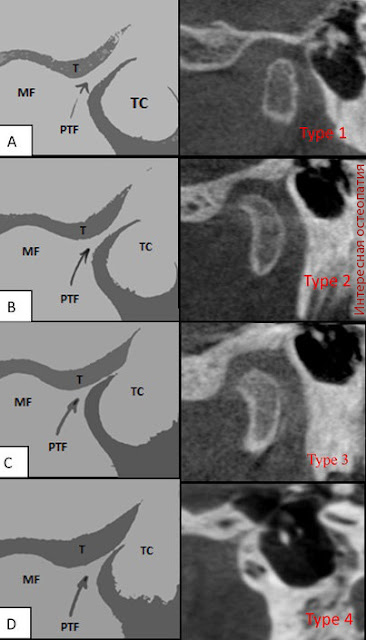

Головка нижней челюсти - валикообразное утолщение эллипсовидной формы, вытянутое в поперечном направлении. Оси, продолженные по длиннику головки, конвергируют у переднего края большого затылочного отверстия, образуя тупой угол. Спереди головки, в крыловидной ямке, прикрепляется латеральная крыловидная мышца. Задняя поверхность головки слегка выпуклая, треугольной формы, с основанием, обращенным вверх. Суставная поверхность нижнечелюстной ямки в 2-3 раза больше головки нижней челюсти. Она имеет эллипсовидную форму. Ямка делится на две части: переднюю - внутрикапсулярную и заднюю - внекапсулярную. Инконгруэнтность между головкой и ямкой выравнивается за счет суставного диска и прикрепления капсулы сустава на височной кости. Внутрикапсулярная часть суставной ямки спереди ограничена скатом суставного бугорка, сзади - каменисто-барабанной щелью. Снаружи ямка ограничена корнем скулового отростка, изнутри - угловой остью клиновидной кости. Форма нижнечелюстной ямки различна и зависит от индивидуальных факторов развития, а также характера зубной окклюзии. Выделяют две крайние формы - глубокую и плоскую.

Одна из характерных особенностей ВНЧС - наличие суставного бугорка, который присущ только человеку. Суставной бугорок, ограничивающий ямку спереди, представляет собой костное возвышение скулового отростка.

Различают две крайние формы бугорка: низкий и широкий бугорок соответствует плоской нижнечелюстной ямке, высокий и узкий - глубокой ямке (рис. 1-25).

Рис. 1-25. Форма суставного бугорка:

а - плоская; б - средневыпуклая; в - крутая